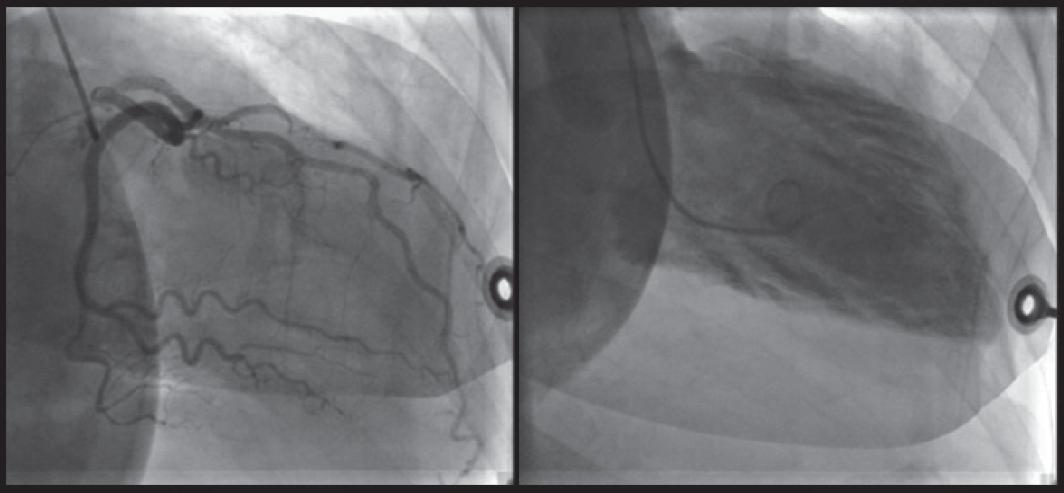

图2 一名患有Takotsubo心肌病女性的心室造影

Takotsubo心肌病患者可出现左心室气球样变,常见于心尖部(75%-80%)或心室中段(10%-20%)。Takotsubo心肌病的确切病理生理机制尚不确定。有证据表明,与应激相关的激素水平急剧升高可导致微血管功能障碍和心肌毒性,进而引起心尖膨胀,肾上腺素系统起到了关键作用。多数患者有情绪或躯体应激的诱因。有报道显示,在2004年日本新泻地震发生后1周内,当地新诊断出的Takotsubo心肌病病例数相当于过去10年诊断的病例数。

图1 左心室心尖部膨胀